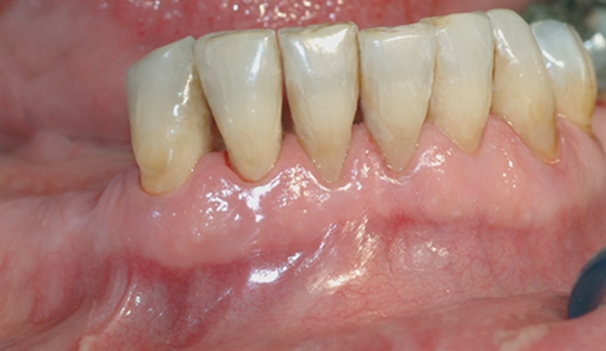

• perio stor 1

perio stor 1

Bildet viser tilsynelatende normale tannkjøttsforhold ved tenner i underkjeven.